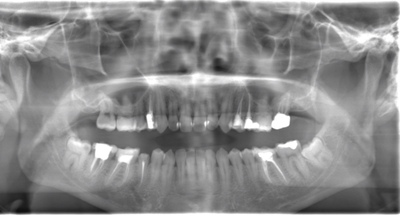

CASE 11

| 年齢・性別 | 33歳・男性 |

| 主訴 | 左上下親知らず抜きたい |

| 抜歯期間 | 30分 |

| 抜歯費用 | 約2,500円(保険内) 別途CT撮影で3,000円 (2022年7月現在) |

| 抜歯内容 | 左上下の親知らず抜歯 |

| 治療方針 |

初めに右下の奥歯が痛いとのことでご来院されました。 右下の親知らずと7番目の歯がカリエスになっていたため、まずは右下の親知らず抜歯と7番目の感染根管治療を行いました。左上下の親知らずもカリエスになっているため、今回抜歯を行いました。 |